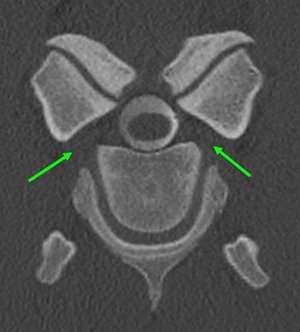

The IVF represents the lateral portion of the spinal canal that connects the intraspinal and extraspinal spaces, serving as the pathway for neurovascular structures exiting the spine. Its boundaries are unique, consisting of two movable joints: ventrally the non-synovial intervertebral joint and dorsally the synovial articular process joint (APJ). In the cervical region, the spinal nerve lies ventral to the articular margin of the APJ, midway between the vertebral notches of adjacent vertebrae. After exiting the IVF, the nerve courses ventromedially toward the caudal tubercle of the transverse process of the cranial vertebra, passing dorsal to the vertebral artery and vein, which run cranially to caudally.

Because the IVF is bordered by two dynamic joints, it is vulnerable to pathological changes affecting either component. Degenerative or developmental alterations – particularly osteochondrosis or osteoarthritis – can narrow the IVF and compress the cervical spinal nerve. Cervical APJ osteoarthritis is a relatively common disorder in horses, especially in the caudal cervical region, and may result in neck pain, stiffness or neurological deficits.